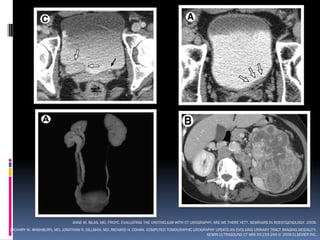

UROGRAFÍA POR TOMOGRAFÍA.

 Estudio de elección para la evaluación renal y

tracto urinario.

 La hematuria es la indicación más común.

 Reemplazó la urografía excretora.

 Fases de acuerdo a la pregunta.

 Bolo simple vs Doble bolo.

 En hematuria monosintomática?

ANNE M. SILAS, MD, FRCPC. EVALUATING THE UROTHELIUM WITH CT UROGRAPHY: ARE WE THERE YET?. SEMINARS IN ROENTGENOLOGY. 2009.

ZACHARY W. WASHBURN, MD, JONATHAN R. DILLMAN, MD, RICHARD H. COHAN. COMPUTED TOMOGRAPHIC UROGRAPHY UPDATE:AN EVOLVING URINARY TRACT IMAGING MODALITY.

SEMIN ULTRASOUND CT MRI 30:233-245 © 2009 ELSEVIER INC.